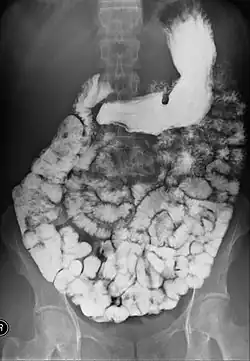

X-ray images are then taken in a supine position at intervals of 20–30 minutes. Real-time fluoroscopy is used to assess bowel motility. The radiologist may press or palpate the abdomen during images to separate intestinal loops. The total time necessary for the test depends on the speed of bowel motility or transit time and may vary between 1 and 3 hours.[17]

The filling of the small intestines can be viewed continuously using fluoroscopy, or viewed as standard radiographs taken at frequent intervals. The technique is a double-contrast procedure that allows detailed imaging of the entire small intestine. However, the procedure may take 6 hours or longer to complete and is quite uncomfortable to undergo.[23]

- Barium follow-through examinations are the most commonly used imaging technique in assessing patients with Crohn's disease, although CT and magnetic resonance imaging are widely accepted as being superior.[1] However Barium examinations remain superior in the depiction of mucosal abnormalities.[24] The features of Crohn's disease are well described by barium follow-through examinations, appearing as a typical "cobblestone pattern", but no information is obtained regarding extraluminal disease.[28] Radiographic imaging in Crohn's disease provides clinicians with objective evaluations of small bowel regions that are not accessible to standard endoscopic techniques.[29] Because of its length and complex loops, the small intestine is the most difficult part of the gastrointestinal tract to evaluate. Most endoscopic techniques are limited to the examination of proximal or distal segments, hence Barium follow-through remains in most centres the test of choice for the investigation of abdominal pain, diarrhoea and in particular diseases manifesting mucosal abnormalities such as coeliac and Crohn's disease.[26]